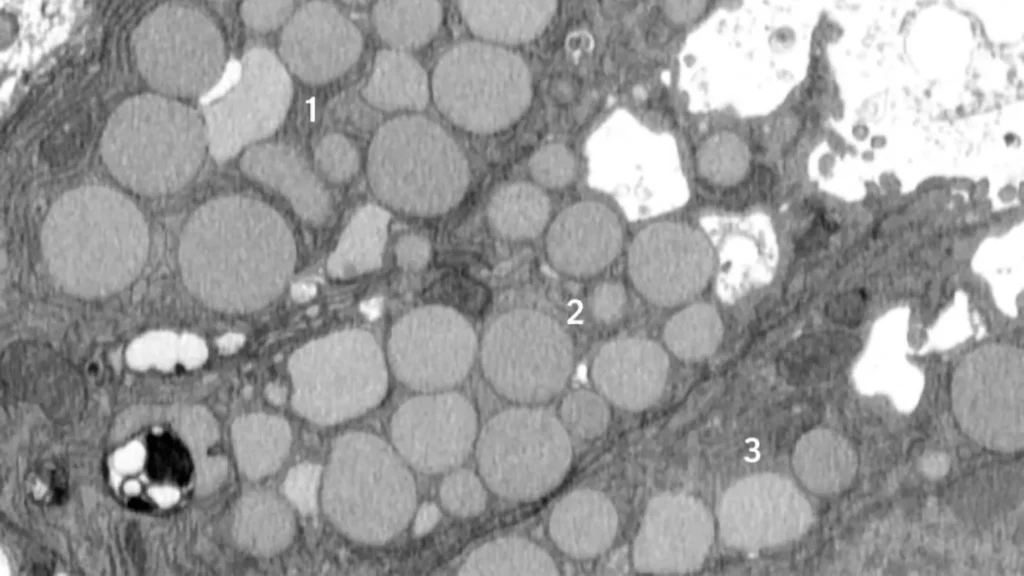

In paligenosis, injured cells shift away from their normal roles and undergo a reprogramming process to an immature state, behaving like rapidly dividing stem cells, as happens during development. Originally, the researchers assumed the decluttering of cellular machinery in preparation for this reprogramming happens entirely inside cellular compartments called lysosomes, where waste is digested in a slow and contained process.

From the start, though, the researchers noticed debris outside the cells. They initially dismissed this as unimportant, but the more external waste they saw in their early studies, the more Brown began to suspect that something deliberate was going on. He utilized a model of mouse stomach injury that triggered the reprogramming of mature cells to a stem cell state all at once, making it obvious that the “vomiting” response — now happening in all the stomach cells simultaneously — was a feature of paligenosis, not a bug. In other words, the vomiting process was not just an accidental spill here and there but a newly identified, standard way cells behaved in response to injury.